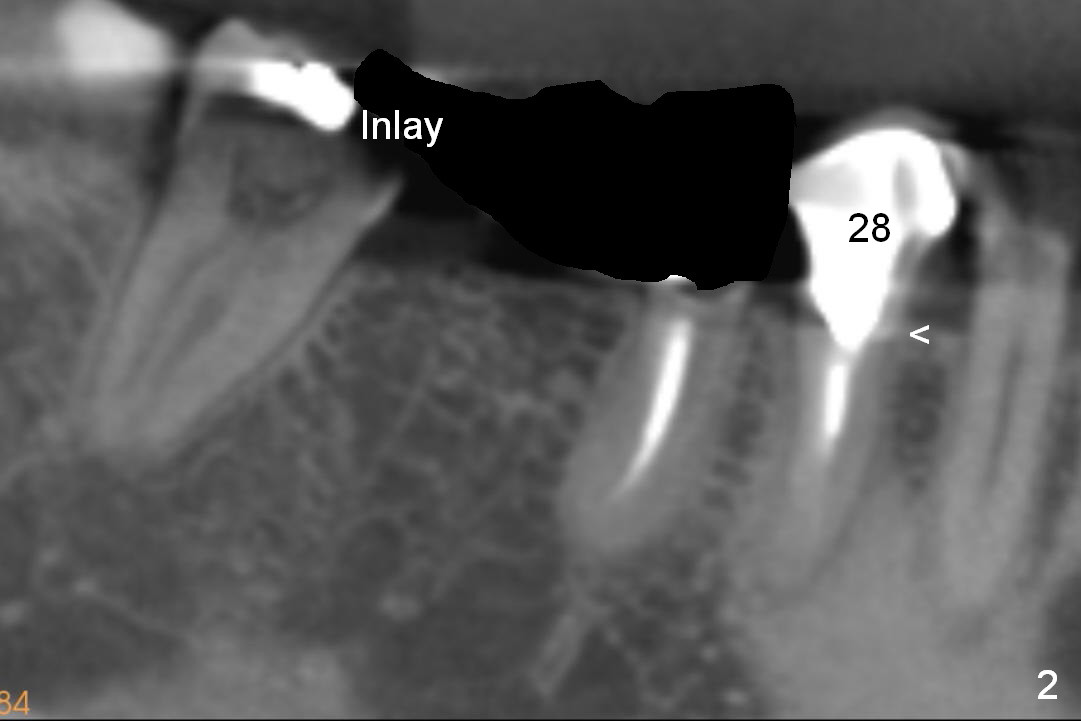

As to #30 osteotomy entry point, it tends to start in the middle of a flat surface (Fig.5' white arrowhead), but it is directly underneath the pontic (P). The trajectory will be not correct. Ideally the entrance point should be at the crest. To avoid slippage, a sharp starter drill will be used. A second advantage is that the osteotomy will be as deep as the previous entry point. There is less likelihood of nerve (N) injury (Fig.5).